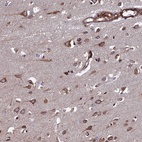

Immunohistochemical staining of human cerebral cortex shows strong positivity in neuronal cells.